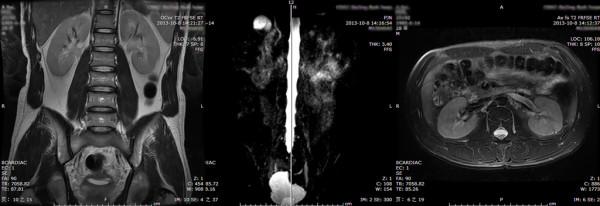

In patients with neurogenic bladder (NB), elevated intravesical pressures can be transmitted to the upper urinary tract, causing hydronephrosis (HN) and ureteral dilation (UD), which are referred to as upper urinary tract dilation (UUTD). Ureteral obstruction at the bladder wall is another cause for UUTD, but is less of a concern. UUTD can lead to chronic renal failure. Therefore, evaluation and protection of UUT function is extremely important in the management for NB. Currently, the most common method by which to detect HN and UD is ultrasonography (US). The Society for Fetal Urology (SFU) established an US HN grading system in 1993, but this system was found to have some defects. The purpose of this study is to describe a new grading system for UUTD, including both HN and UD, based on magnetic resonance urography (MRU) and to correlate the new grading system with the SFU grading system for HN.

A retrospective review of 70 patients with unilateral or bilateral UUTD was completed. Ninety-five sides in patients with UUTD were graded by the MRU-UUTD and SFU-HN grading systems. The results from the two grading systems were compared for each UUTD.

RESULTS

The MRU-UUTD grading system revealed the following percentages for each grade: grade 0, 0; 1, 10.5%; 2, 19%; 3, 42.1%; and 4, 28.4%. The SFU-HN grading system revealed the following percentages for each grade: 0, 0; 1, 10.5%; 2, 19%; 3, 36.8%; and 4, 33.7%. There was no significant systematic difference between the two grading systems (p > 0.05), but a significant difference between grades 3 and 4 (p < 0.05).

在神经源性膀胱(NB)患者中,升高的膀胱内压可向上尿路传递,导致肾盂积水(HN)和输尿管扩张(UD),即上尿路扩张(UUTD)。膀胱壁的输尿管梗阻也是 UUTD 的另一个原因,但不太常见。UUTD 可导致慢性肾衰竭。因此,在 NB 的管理中,评估和保护 UUT 功能至关重要。目前,检测 HN 和 UD 最常用的方法是超声检查(US)。胎儿泌尿外科学会(SFU)于 1993 年建立了超声 HN 分级系统,但该系统存在一些缺陷。本研究旨在描述一种基于磁共振尿路成像(MRU)的新的 UUTD 分级系统,包括 HN 和 UD,并将新分级系统与 SFU 的 HN 分级系统进行相关性分析。

对 70 例单侧或双侧 UUTD 患者进行回顾性分析。95 侧 UUTD 患者的 MRU-UUTD 和 SFU-HN 分级系统进行分级。比较两种分级系统对每侧 UUTD 的分级结果。

结果

MRU-UUTD 分级系统显示每个等级的百分比如下:0 级,0;1 级,10.5%;2 级,19%;3 级,42.1%;4 级,28.4%。SFU-HN 分级系统显示每个等级的百分比如下:0 级,0;1 级,10.5%;2 级,19%;3 级,36.8%;4 级,33.7%。两种分级系统之间没有显著的系统差异(p>0.05),但 3 级和 4 级之间有显著差异(p<0.05)。